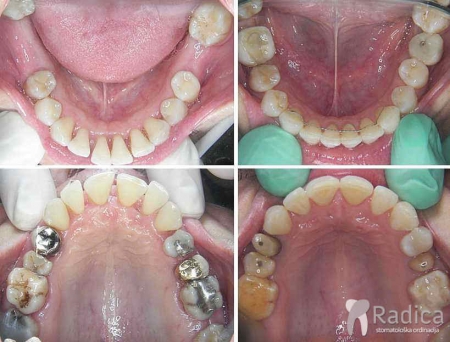

U sljedećem primjeru je fiksna ortodontska terapija rađena samo u donjoj čeljusti. Nakon toga su napravljeni novi protetski radovi u gornjoj i donjoj čeljusti – rad dr. Gorana Radice.

Na sljedećoj slici se mogu vidjeti početak i kraj ortodontske i protetske terapije. Protetske radove radio je dr. Goran Radica.

U sljedećem primjeru je fiksna ortodontska terapija rađena samo u donjoj čeljusti. Nakon toga pacijent je upućen svom stomatologu koji je napravio nove protetske radove u gornjoj i donjoj čeljusti.